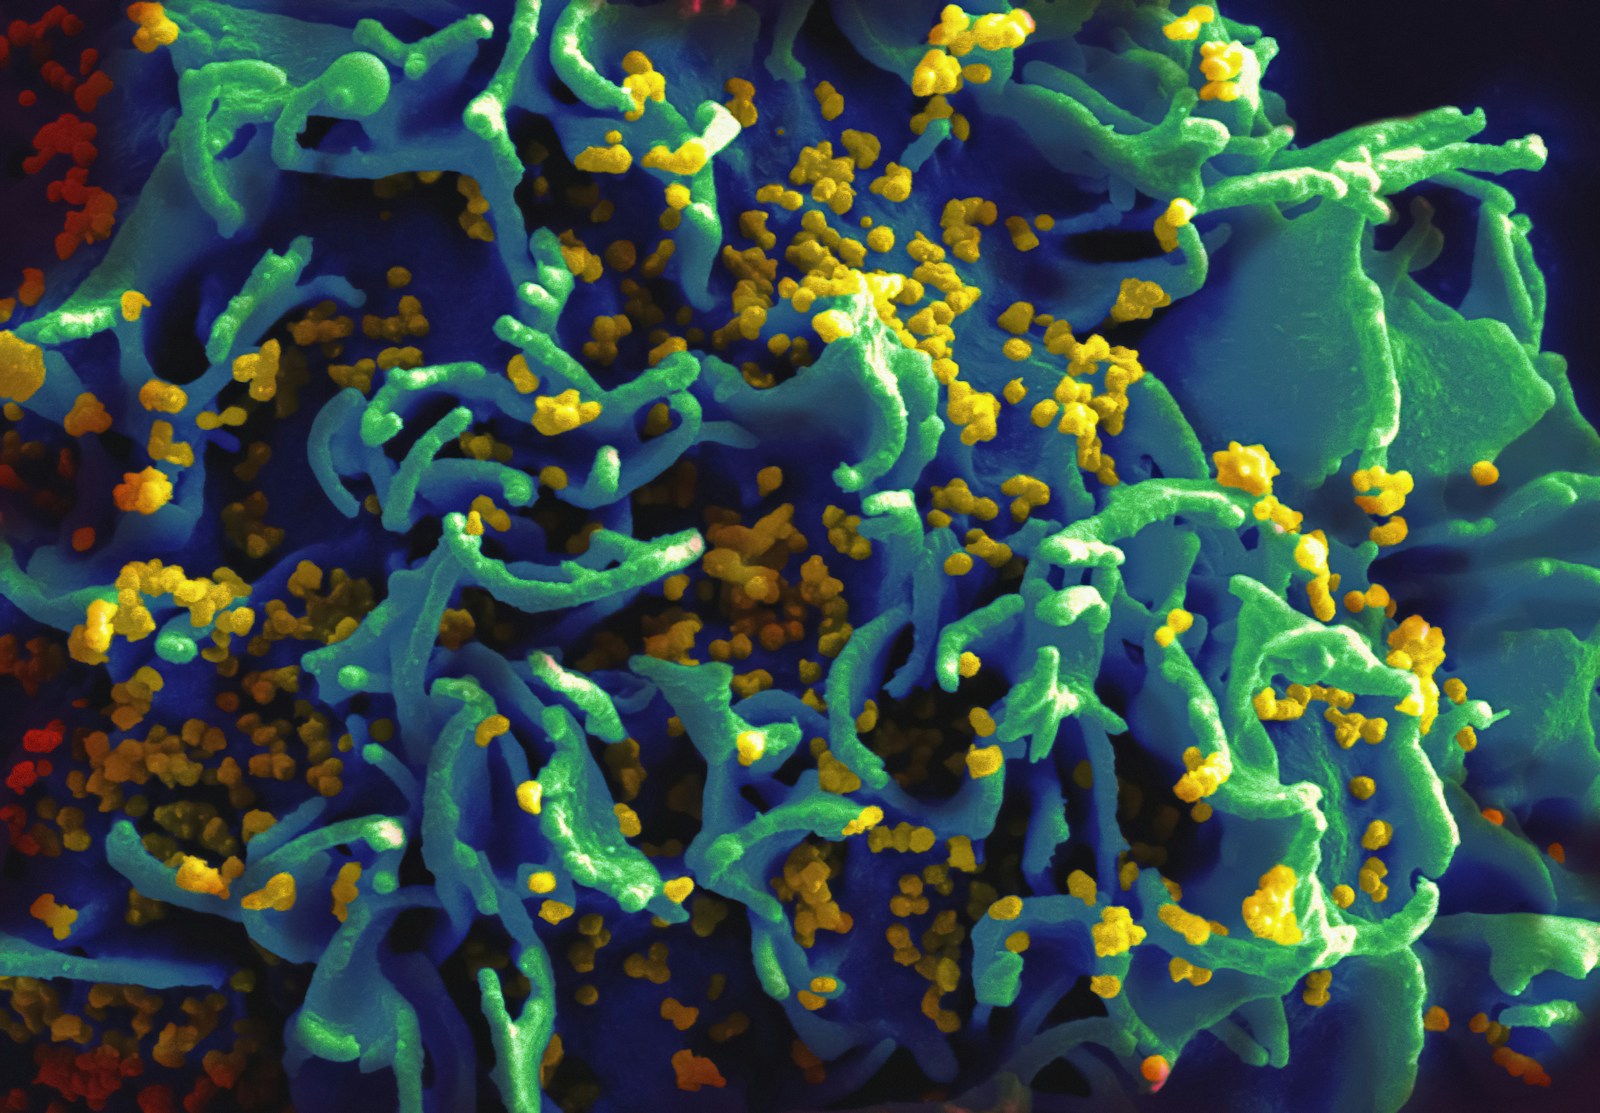

Sú ľudia, ktorí sa prakticky nemôžu nakaziť HIV

Štatisticky je to 1 % ľudí severoeurópskeho pôvodu, ktorí môžu vďačiť vzácnej genetickej mutácii nazývanej CCR5 delta 32. Táto abnormalita spôsobuje menšiu veľkosť špecifického receptoru, čo vo výsledku znamená, že vírus HIV nemôže preniknúť do buniek a množiť sa v nich. Vedci sa snažili na základe týchto ľudí vyvinúť liek, ktorý by bol úspešný v boji proti HIV. Zatiaľ je to ale v štádiu skúmania.